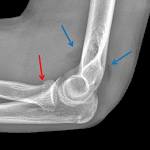

Age: 13

Sex: Male

Indication: Fall

- Acute mildly impacted radial head fracture

- Elbow joint effusion

- Radial head fracture

Acute mildly impacted radial head fracture.

Elbow joint effusion.

No malalignment.

- Radial head fractures are the most common elbow fractures in older adolescents and adults

- Just like supracondylar fractures, these can be subtle, with an elbow joint effusion sometimes being the only radiographic finding

- Make sure to always look for and comment on joint alignment